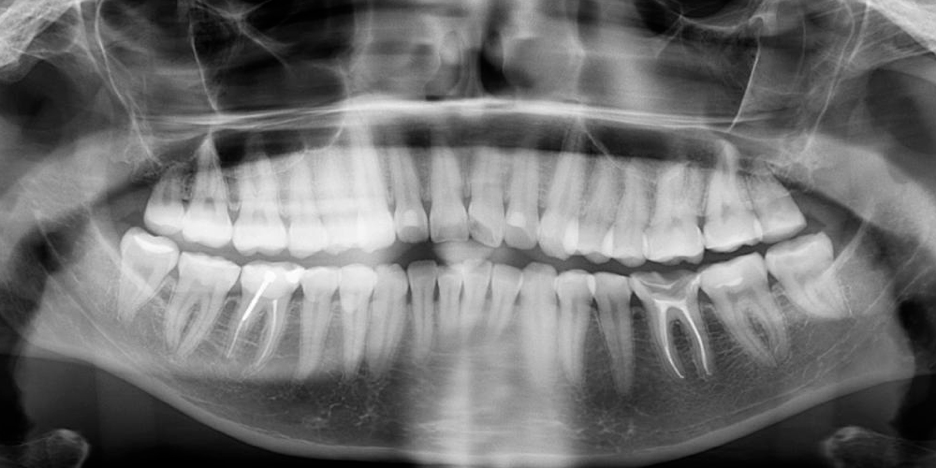

Посмотрите на рентген-снимок, вот так могут выглядеть зубы мудрости, которые расположены не совсем там, где нужно. А именно – глубоко в кости, еще и в кривом положении. Как думаете, нужно ли такие сохранять? А вот ответ, кстати, не так однозначен, как кажется! Читайте материал дальше – расскажем все подробности.